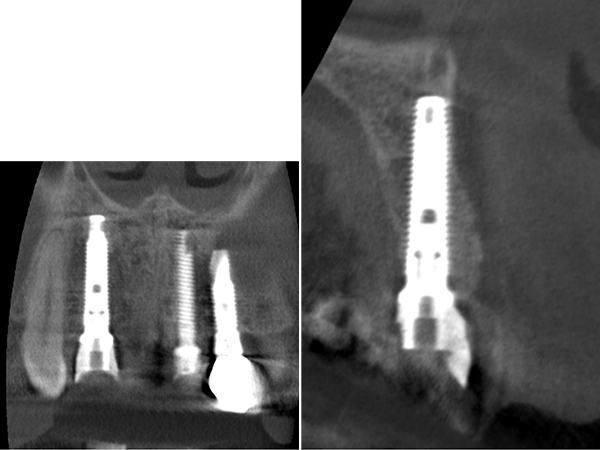

CTによる診査

CTを撮影し、歯根の長さや根尖病変の大きさを精査しました。

CTによるシミュレーション

2|

|1

1次手術手術後のレントゲン写真

2|

|1

レントゲン写真による評価